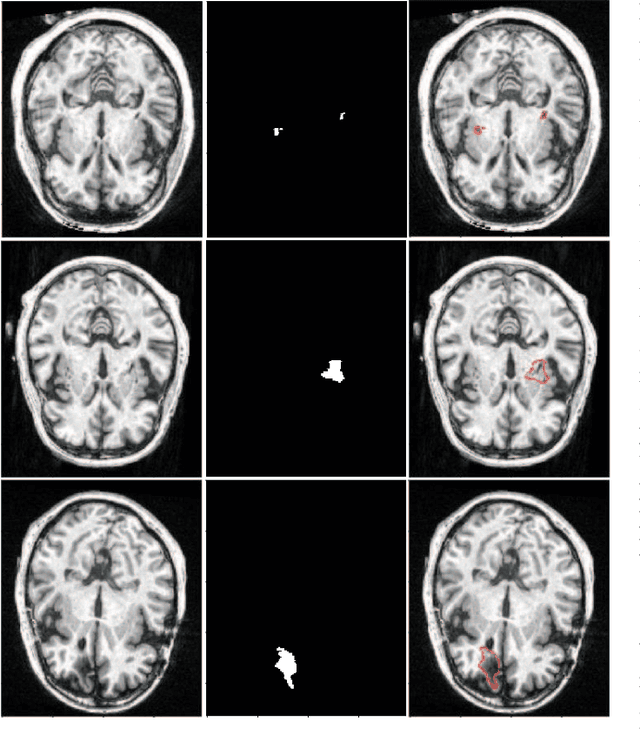

Abstract:Assessing the location and extent of lesions caused by chronic stroke is critical for medical diagnosis, surgical planning, and prognosis. In recent years, with the rapid development of 2D and 3D convolutional neural networks (CNN), the encoder-decoder structure has shown great potential in the field of medical image segmentation. However, the 2D CNN ignores the 3D information of medical images, while the 3D CNN suffers from high computational resource demands. This paper proposes a new architecture called dimension-fusion-UNet (D-UNet), which combines 2D and 3D convolution innovatively in the encoding stage. The proposed architecture achieves a better segmentation performance than 2D networks, while requiring significantly less computation time in comparison to 3D networks. Furthermore, to alleviate the data imbalance issue between positive and negative samples for the network training, we propose a new loss function called Enhance Mixing Loss (EML). This function adds a weighted focal coefficient and combines two traditional loss functions. The proposed method has been tested on the ATLAS dataset and compared to three state-of-the-art methods. The results demonstrate that the proposed method achieves the best quality performance in terms of DSC = 0.5349+0.2763 and precision = 0.6331+0.295).